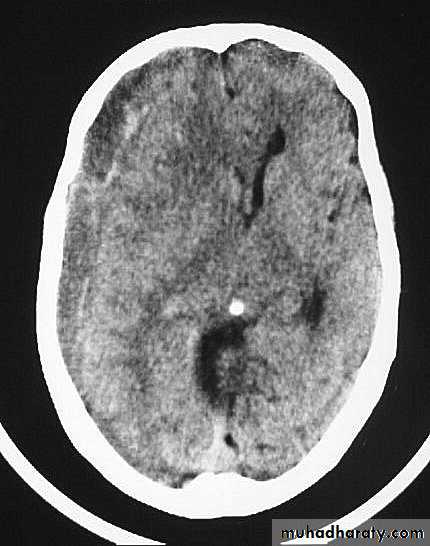

c. Intracerebral Haematoma

This is the least common of traumatic haematoma.They are due to areas of traumatic contusion coalescing into a contusional haematoma.

CT scan: appear as hyperdence lesions with associated mass effect and midline shift.Large intracerebral haematomas should be evacuated unless the patient’s neurological state is improving.

Small inracerebral haematomas may not require removal, but be aware that they can expand.